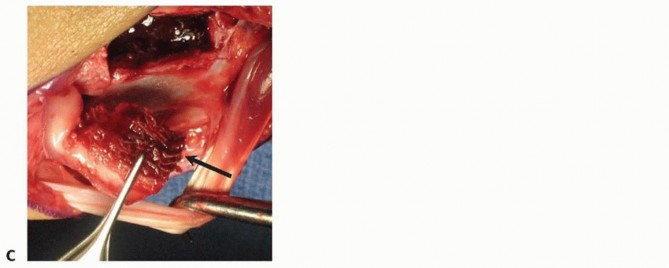

TECH FIG 4 • A. The palmar distal radius graft is harvested through the distal portion of the Henry approach to the distal forearm. B. The palmar carpal artery is exposed distal to superficial aponeurosis of the pronator quadratus. (continued)

TECH FIG 4 • (continued) C. The scaphoid nonunion site (at tip of Freer elevator) is débrided to remove fibrous tissue. D. The palmar corticocancellous graft (in forceps) is rotated into the nonunion site. E. The graft is press-fit into the nonunion site and secured with internal fixation.

Periosteum on either side of the palmar carpal artery is incised, and the artery is gently mobilized laterallyto the radial artery.Bone graft harvest from the ulnar half of the distal radius is initiated by periosteal incision with a scalpel, followed by osteotomy and elevation with small osteotomes.Incision through the radioscaphocapitate ligament exposes the scaphoid nonunion site and allow for removal of fibrous tissue (TECH FIG 4C).